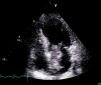

On physical examination she was hemodynamically stable, with no relevant alterations. The 12-lead electrocardiogram (ECG) showed sinus rhythm and ST-segment depression in V4, with negative T waves in V4-V5 and flattened T waves in V6 and frontal leads (Figure 1). Laboratory tests revealed hemoglobin 11.3g/dl, erythrocyte sedimentation rate 84mm, C-reactive protein 6.14mg/dl, troponin I 1.89ng/dl (rising slightly on the second assessment to 2.02ng/dl) and CK-MB 8.4ng/ml. She was therefore admitted to our coronary care unit with a diagnosis of non-ST elevation acute myocardial infarction. Transthoracic echocardiography showed moderate to severe left ventricular systolic dysfunction, with apical akinesia and hypokinesia of the mid-apical segments of the anterior and lateral walls and interventricular septum. As well as these wall motion abnormalities, a large left atrial mass was observed attached to the interatrial septum, coral-like and with a friable appearance, measuring 46mm on its longest axis, the most apical portion of which prolapsed into the left ventricle in diastole over the anterior leaflet of the mitral valve, without causing fixed obstruction to flow in the left ventricular outflow tract (Figure 2). Given the high suspicion of myxoma, transesophageal echocardiography was immediately performed (Figure 3), which confirmed the findings of transthoracic echocardiography. In view of the risk of imminent embolization, the cardiothoracic surgery department at our referral hospital was contacted and accepted our patient after coronary angiography, which revealed no significant lesions (Figure 4).